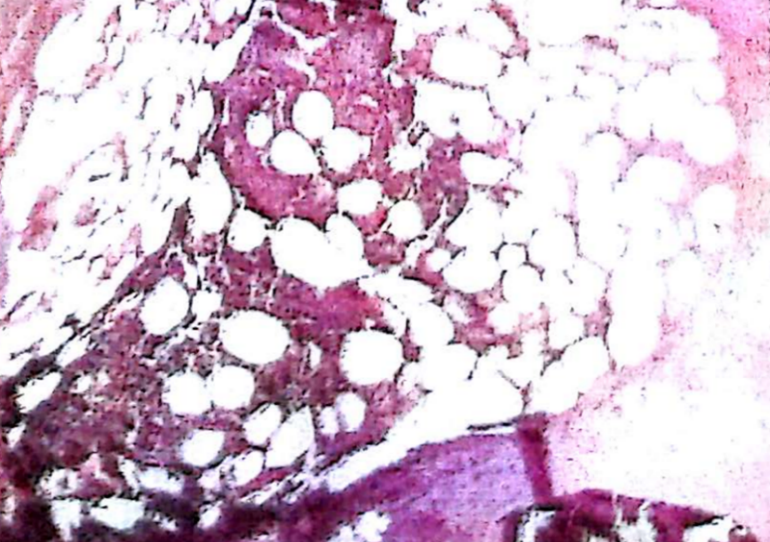

The biopsy reported inflammatory infiltrate of polymorphonuclear and mononuclear cells, as well as collagen hyalinization (Figure 6). These findings confirmed the diagnosis of PG. She is discharged 8 days after the treatment with Betamethasone dressings, and outpatient follow up of the lesions showed granulation tissue and appropriate healing (Figure 7).

Figure 6. Inflammatory infiltration of polymorphonuclear and mononuclear cells, fibrosis and hyalinization of collagen and elastic fibers, basal cell hyperplasia and hyperkeratosis with mild acanthosis, compatible with classical pyoderma gangrenous